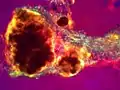

A tophus inside a knee joint being removed by arthroscopic surgery Tophus of uric acid crystals from toe joint fluid (100x polarized light)

Tophus of uric acid crystals from toe joint fluid (100x polarized light)